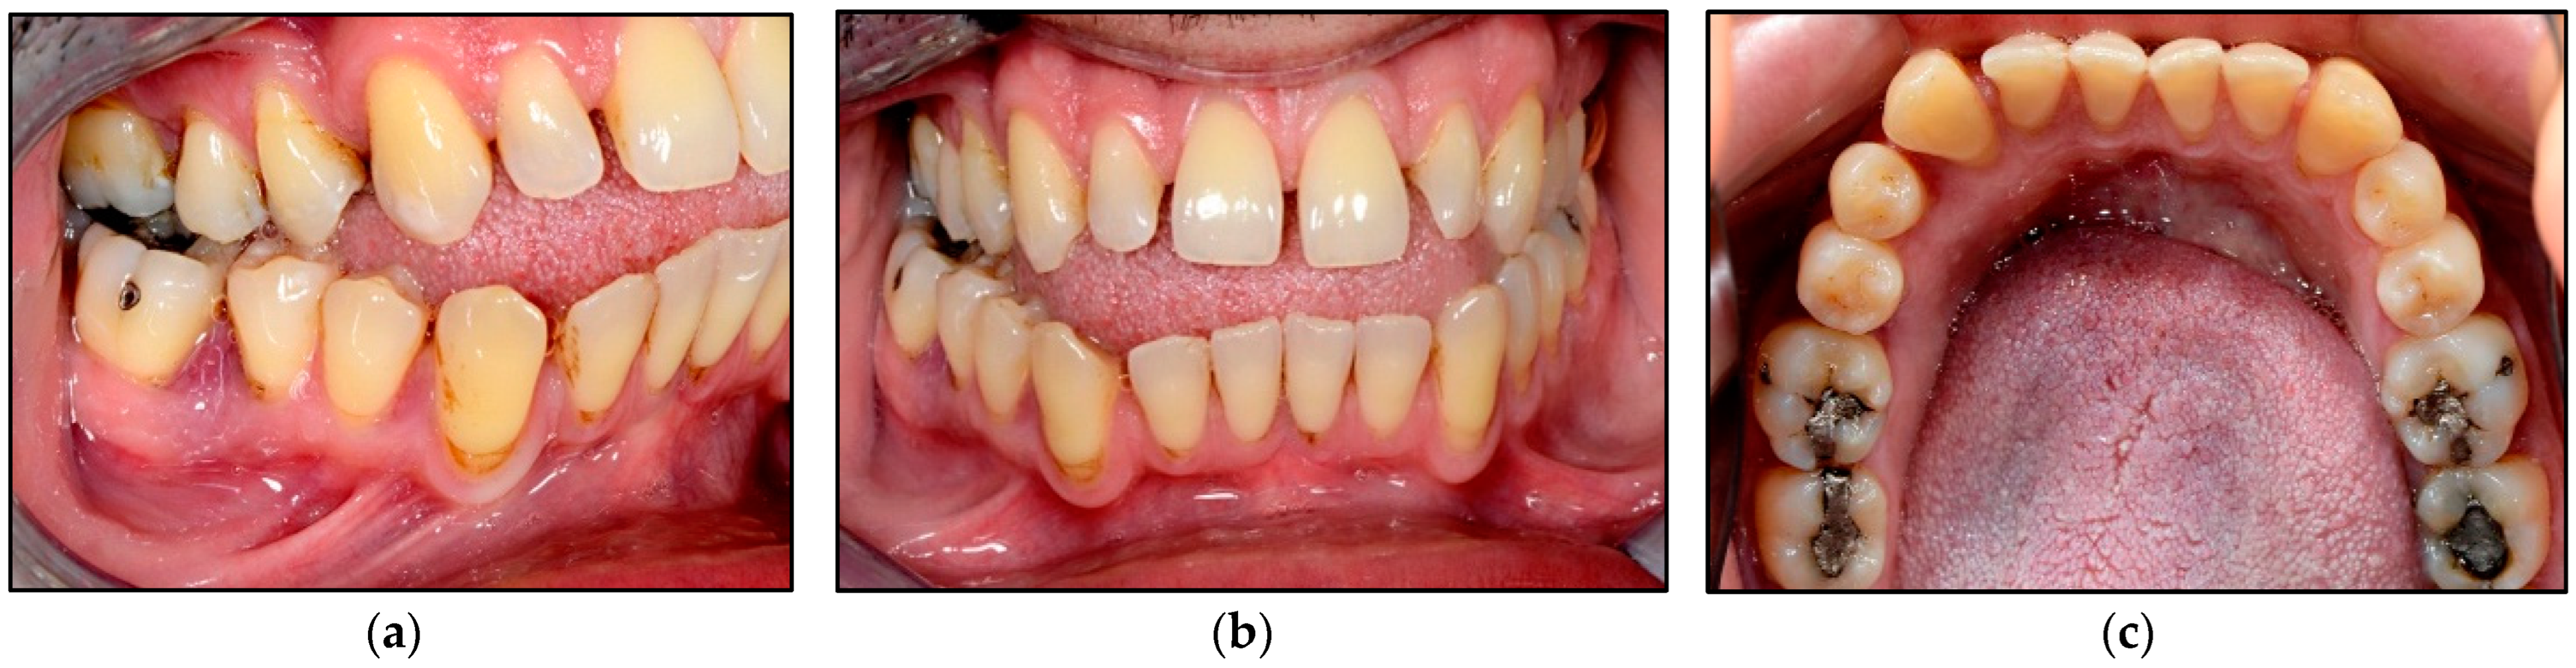

In terms of wound healing, Figure 6 shows evidence of a band of re-epithelisation (Grade IV) of the mucosal tissues buccally (Figure 6a) and lingually (Figure 6b) on the 4th day post-laser treatment. Additionally, the clinical photos (Figure 6) show that the gingival contouring of LR5 and LR6 buccally and lingually was well maintained as well as the interdental papilla without evidence of gingival recession or lesion recurrence.

Figure 6. Clinical photos illustrating the outcomes of the laser treatment on the 4th day post-operatively. (a) shows Grade IV re-epithelisation of the mucosal tissue buccally as well as lingually (b) with well-maintained integrity of the gingival contouring and interdental papilla between LR5 and LR6.

At two weeks follow-up at the clinic, Figure 7a,c shows the treated sites exhibiting a complete epithelisation scoring Grade V with no evidence of lesion recurrence, and the gingival contouring around the LR5 and LR6 was healthy and pinkish in colour without evidence of gingival recession. The gingival zenith of the treated sites was aligned with the contralateral sites (Figure 7b,c). The evaluation of wound healing grading was performed by two healthcare professionals (the operator and the laser nurse) at all timepoints. The patient cancelled his 6-month follow-up appointment, but he confirmed no lesion reoccurrence via telephone call.

Figure 7. Shows clinical photos of the laser treated sites at two-weeks post-operatively. (a) an intraoral right lateral view of LR5 and LR6 demonstrates a complete re-epithelisation of the buccal mucosal tissue with no evidence of lesion recurrence or gingival recession. (b) an intraoral frontal view shows that the gingival zenith of the treated sites is aligned with the contralateral sites, demonstrating that laser-assisted surgery maintains the integrity of the gingival contour. (c) lingual view of the lower teeth shows a complete re-epithelisation of the lingual mucosal tissue of the treated sites (LR5 and LR6) with no evidence of lesion recurrence or gingival recession, as well the gingival zenith of the treated sites is aligned with the contralateral sites. This demonstrates that laser-assisted surgery does not jeopardise the integrity of the gingival contour.